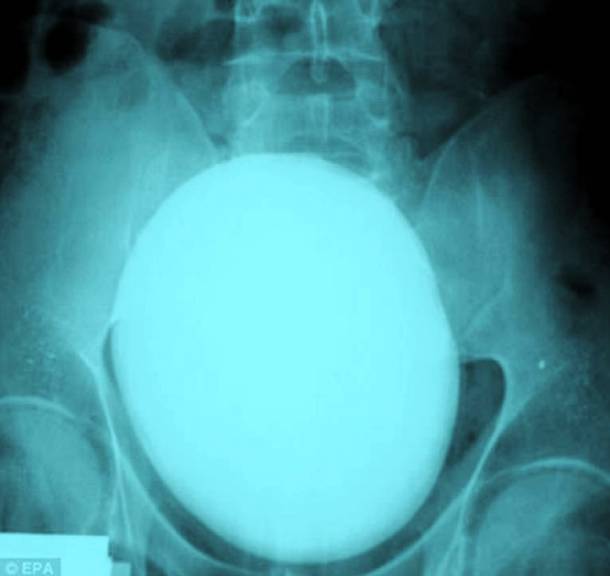

18. A Seven Inch Kidney Stone

This kidney stone seems so huge that it could not possibly be real. But it is. This kidney stone was found inside a patient in Hungary and it was a massive 7-inches long and wide. Thankfully, it was successfully removed which was a huge relief to the patient.Advertisement